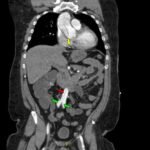

Acute aortic dissection is a life-threatening event caused by separation of the aortic layers that requires prompt management and surgical consultation. We present the case of a 53-year-old male who developed acute, severe chest pain radiating to his back at a community hospital and was transferred to a tertiary center for definitive surgical management. The patient’s aortic dissection was diagnosed via computed tomography angiography. He was started on rate-control and blood pressure medications, and was admitted emergently to the operating room. Emergency physicians should obtain immediate surgical consultation, promptly start medications for rate and blood pressure control, and administer analgesia in order to stabilize their patient and decrease the shear forces that would further propagate an aortic dissection.